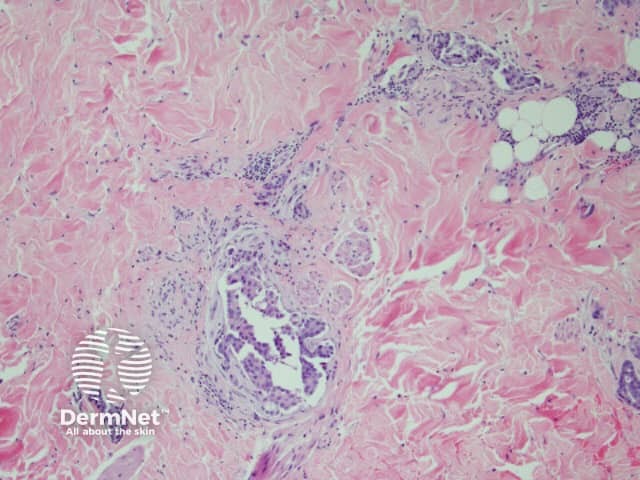

Histological findings of inflammatory carcinoma is distinctive with the deposition of tightly packed malignant cells within the superficial and deep lymphatics without the pathologic evidence of acute inflammation, such as neutrophils, although the lesions look clinically red and inflamed. Dermal lymphatic invasion is considered to be the hallmark of CE. 8

Figure 1